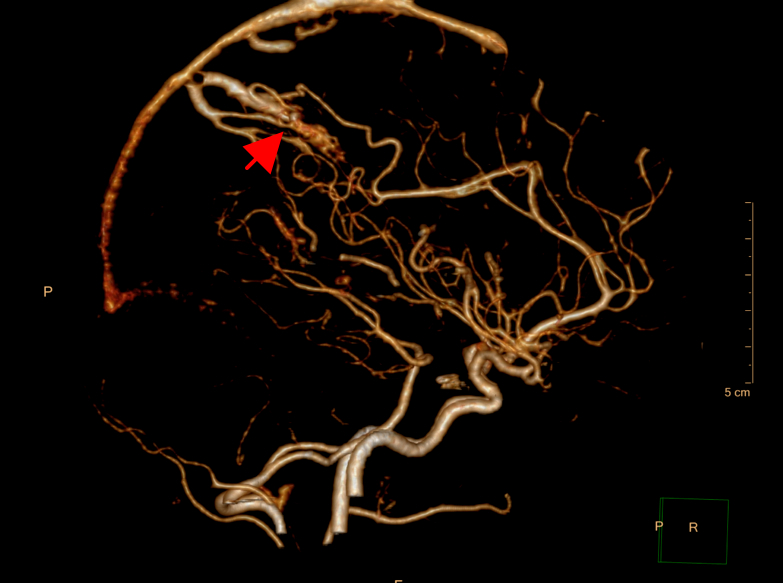

Giulio (nome di fantasia) è un ragazzo di quindici anni che viene condotto in Pronto Soccorso (PS), trasferito da un presidio riabilitativo territoriale, per dolore inguino-scrotale. La sua anamnesi è silente fino al mese prima, quando, in pieno benessere, ha presentato cefalea acuta, vomito a getto e perdita di coscienza. La TC encefalo ha documentato la presenza di un ematoma intracranico parietale destro atipico e l’angiografia ha dimostrato una malformazione artero-venosa (MAV) (Figure 1-3).

È stato sottoposto a intervento neuroradiologico di embolizzazione della MAV e a successivo intervento neurochirurgico di evacuazione dell’ematoma cerebrale. La TC post-operatoria ha documentato l’ottimale evacuazione dell’ematoma e l’angiografia ha escluso residui. Clinicamente il decorso post-operatorio è stato caratterizzato da un rapido recupero della coscienza ma con lieve emiparesi sinistra ed eminattenzione sinistra, per cui Giulio viene trasferito presso un Centro riabilitativo. Qui ha eseguito per 11 giorni terapia con enoxaparina sc e un percorso riabilitativo, arrivando a una completa risoluzione del quadro clinico.